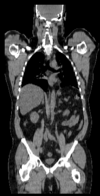

lleft whole body CT baseline lleft whole body PET baseline lleft whole body CT follow-up lleft whole body PET follow-up

CT: 512 x 512 x 267

0.97 x 0.97 x 3.27 mm

PET: 128 x 128 x 267

4.7 x 4.7 x 3.3 mm

CT: 512 x 512 x 195

0.98 x 0.98 x 5.0 mm

PET: 168 x 168 x 195

4.1 x 4.1 x 5 mm